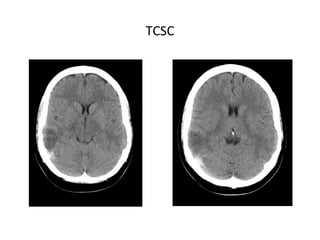

TCSC

TC

• TC SIN CONTRASTE IV

Para descartar patologías con síntomas similares (infartos

arteriales, tumores o procesos infecciosos), aunque en un

25% de las TVC podemos no encontrar hallazgos

significativos.

SIGNOS DIRECTOS

Hiperdensidad homogénea durante las 2 primeras semanas:

- Signo de la cuerda densa: por trombosis aguda de venas

corticales.

- Seno lateral denso

- Vena yugular densa

- Triángulo denso (SSS)

SIGNOS INDIRECTOS

- Infartos no hemorrágicos: Frecuentes. (subcortical, sin

distribución arterial típica, proximal al seno afectado).

- Infartos hemorrágicos: 10-50% de los casos, pueden ser

profundos, superficiales o multifocales.

- Edema cerebral difuso.

- Colapso ventricular.